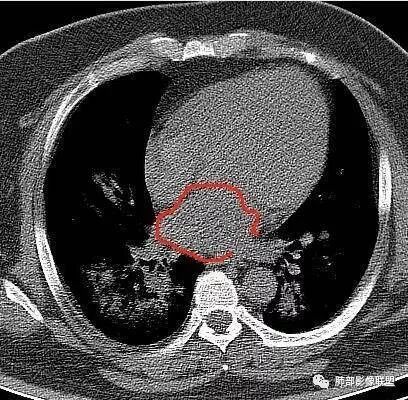

青年男性、急性病史、发热、咳嗽、常规抗炎无效病灶沿支气管血管束分布  GGO+实变边界模糊部分沿胸膜下分布哪几种可能?

南边:1、感染:间质分布——病毒、支原体,支原体一般树芽征明显,累及小气道多,而且临床轻,不太支持2、血管炎,需要相关病史3、肺水肿:心脏不大,无胸水、无中央间质增厚、小叶间隔增厚,不太支持4、PAP,病史影像表现都不支持初学者:可能是病毒,但是好像并不是我们常见的流感病毒实变为主,腺病毒?就是太多灶了一点

起病突然,高热,双肺多发磨玻璃影及实变影,胸膜下分布为主,不具有肺门分布优势,也没有小叶间隔增厚,一般会首先考虑病毒感染,尤其是甲流。